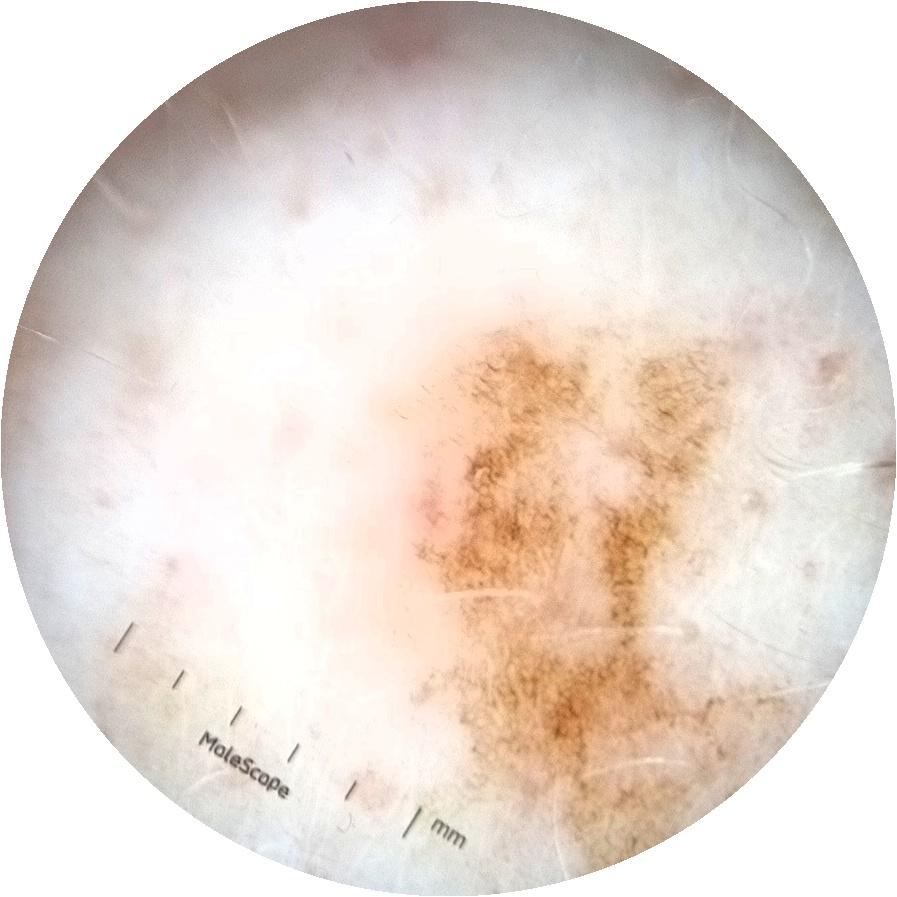

ISIC_3754278

MEL-SELF Trial, https://www.sydney.edu.au/medicine-health/our-research/research-centres/melself-project.html

Clinical

Field Value

acquisition_day 135

age_approx 65

anatom_site_1 Upper extremity

anatom_site_general upper extremity

diagnosis_1 Benign

diagnosis_confirm_type single image expert consensus

image_type dermoscopic